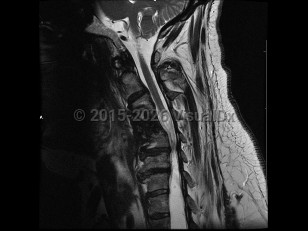

Syringomyelia is a cavity or syrinx within the spinal cord that can expand over time. Although the underlying pathophysiology is incompletely understood, syringomyelia is thought to form because of abnormal flow of the cerebrospinal fluid (CSF), and this dysfunctional pressure gradient causes fluid to build up in the spinal cord. Acquired syringomyelia may result from hydrocephalus, infection, inflammation, trauma or spinal cord injury, intramedullary or extramedullary tumors, spinal canal stenosis, vascular malformations, or bony abnormalities. Overall, the prevalence of syringomyelia varies worldwide, ranging from approximately 2-8 per 100 000. Age of onset varies by cause.

Symptoms depend on the location of the lesion; most occur in the cervical region, between C2 and T9. In some cases, patients are asymptomatic, and syringomyelia is an incidental finding on imaging. Cervical syringomyelia typically manifests as early impairment of temperature and pain sensation in a cape-like distribution over the back and arms, and weakness that is greater in the bilateral upper extremities compared with the bilateral lower extremities. There may also be chronic pain. Neurologic examination may be notable for loss of reflexes, light touch, vibration, and joint position sense; weakness and atrophy of the hands; and lower extremity spasticity and hyperreflexia. Bladder, bowel, and erectile dysfunction can occur as late manifestations.

Prognosis depends on the underlying etiology as well as the location and extent of the lesion. However, syringomyelia typically progresses slowly and leads to functional impairment, necessitating surgical intervention. Even after surgical intervention, a treatment-refractory central pain syndrome often persists.